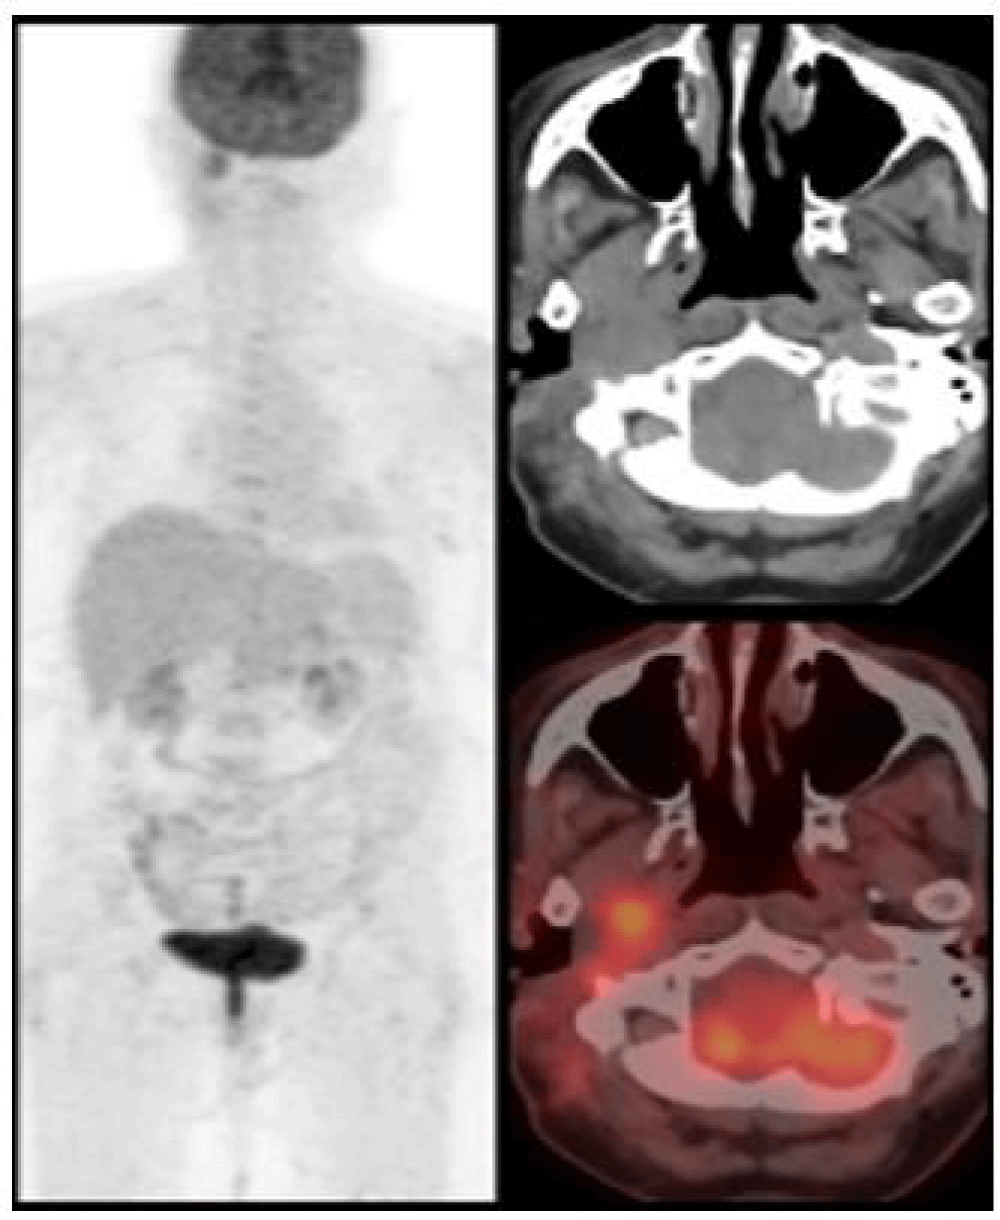

We report a case of 68 years old female with a past history of adenoid cystic carcinoma of right parotid gland post superficial parotidectomy and adjuvant radiotherapy in 2004. Now with complaints of right ear discharge and ear ache since 6 months, on further detailed and systematic evaluation, revealed a mass lesion in the EAC with extension into the infratemporal fossa (Figure 1) which was confirmed to be a well-differentiated Squamous Cell Carcinoma (SCC) on biopsy. After obtaining proper consent and ethical clearance, the patient underwent surgical de-bulking followed by adjuvant EBRT to post-operative residual disease and elective irradiation of ipsilateral nodal levels II and III using the VMAT technique (Figure 2) to a total dose of 66 Gy delivered in 33 fractions, 2 Gy per fraction. The patient tolerated radiotherapy well and was placed under regular follow-up. 12 weeks post EBRT patient was assessed clinically and radiologically with 18F-FDG whole-body PET-CT scan which showed complete morphological and metabolic response (Figure 3). The patient is under surveillance and is doing well.

Download Image

Figure 1: Pre EBRT PET CT Scan findings revealing 2.1x1.4x3.2 cm lesion in the right EAC extending to the Infratemporal Fossa (ITF).